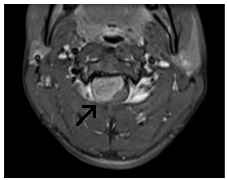

Jobb-paramedián, foraminalis porckorongsérv C6-C7.

Súlyos trauma a nyaki gerinc: a törés-zavar a C5 csigolya test, súlyos tömörítés az agytörzs, jeleivel gerincvelő-ödéma, a teljes gerinccsatorna szűkület szintjén a törés. MR kép prevertebrális vérömleny.

T1VI T2VI (keverjük) T2VI

Meningeoma felső nyaki régióban a gerinccsatorna

T2VI T1 (kontraszt)